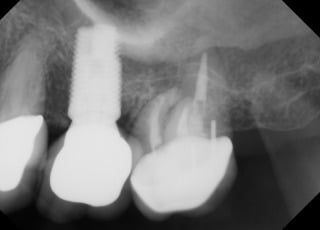

Charles P.

This patient had an Implant placed to replace a missing molar which had been removed due to infection.